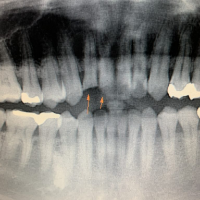

症例2

治療方法 変色した歯:セラミッククラウン法

詰め物跡のヒビ:ダイレクトボンディング

ホワイトニング

治療期間 2ヶ月

治療費用 ファイバーコア+セラミッククラウン 1歯 ¥181,500(税込)

ダイレクトボンディング 1歯 ¥33,000(税込)

治療の副作用.リスク 詰め物は経年劣化で変色する

歯を削る必要がある

セラミッククラウン法+ダイレクトボンディング+ホワイトニング

神経を取った歯の根もとにヒビが入っていることと変色がお悩みでした。神経を取ってから10年ほど経過すると変色や歯の劣化が進み、見た目だけでなく歯の強度も損なわれます。

このような場合は、歯の内部に土台を入れて補強した後にセラミッククラウンで被せることで強度と審美性が得られます。